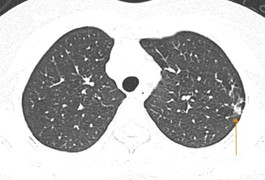

(VTC News) - Mắc cúm A, người đàn ông bị biến chứng nguy kịch, phổi tổn thương hai bên, phải nhập viện cấp cứu và đặt ECMO.

(VTC News) - Cúm có thể gây ra biến chứng viêm phổi và tử vong, vì vậy chúng ta không nên chủ quan với căn bệnh này.